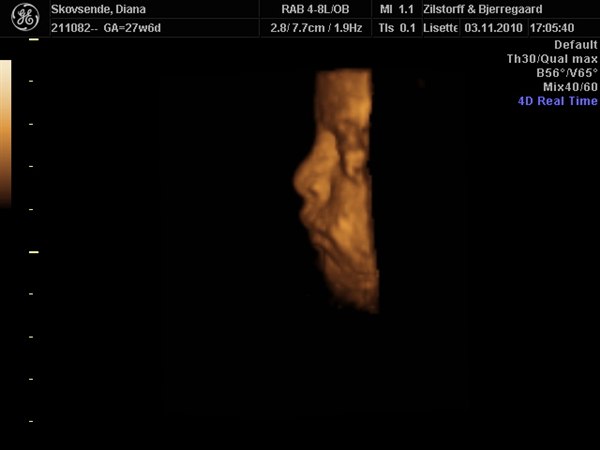

Wauw, hvor er det altså vildt, det man kan se på sådan nogle 3D-billeder. Jeg er vild med nr. 2 billede, der viser hende i profil. Kan I genkende jer selv i det?

Elsker billedet i profil!!!

Profil billedet er bare skøøønt!!

Ja vi er også rigtig glade for profil billed det lykkes hende lige at få hende drejet nok til at kunne tage det.

Hvor er det dejligt at det gik godt. Er fuldstændig pjattet med profilbilledet - det er rigtig godt!